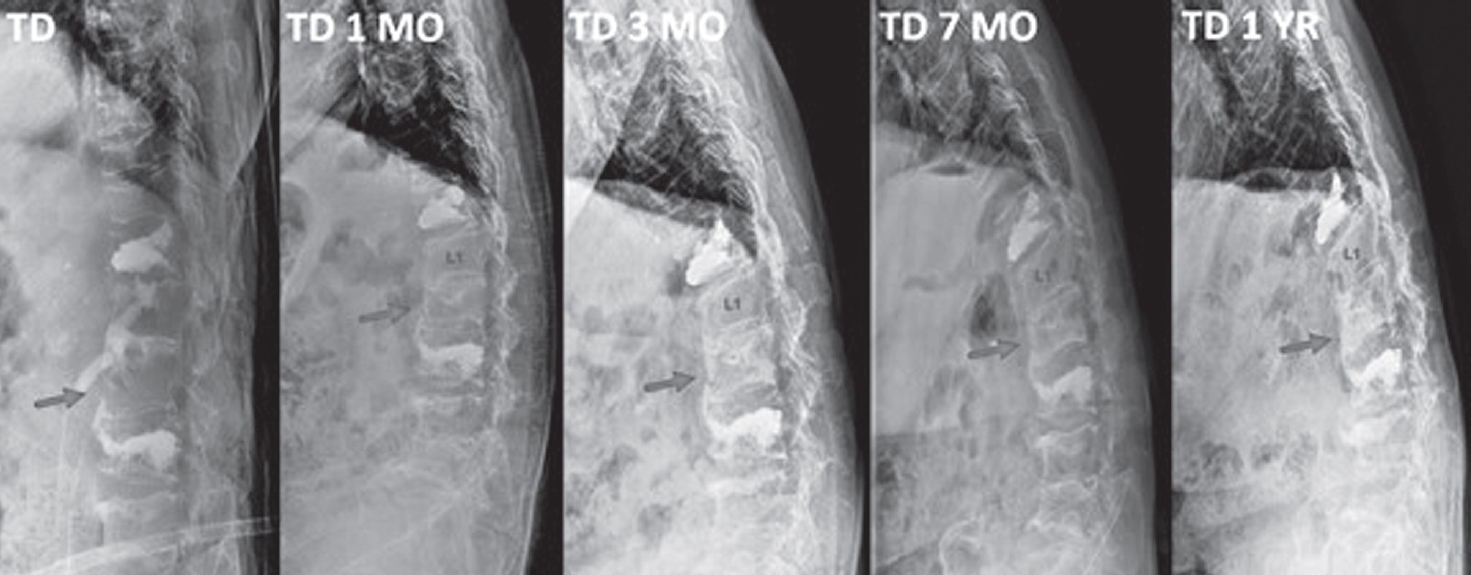

At the two-month follow-up, radiographs demonstrated no further collapse of the L2 vertebra, and her body cast was exchanged for a thoracolumbosacral orthosis (TLSO). Back pain progressively improved. By three months, radiographs showed early signs of fracture consolidation accompanied by improved ambulation and increased walking distance (Fig. 2).

At six months, she was able to ambulate with a walker. After completing six monthly doses of romosozumab, therapy was transitioned to denosumab for long-term maintenance. One-year follow-up CT demonstrated complete consolidation of the L2 fracture with substantial intravertebral bone fill-in (Fig. 3).

Fig. 2.

Serial follow-up radiographs showing progressive healing of the L2 compression fracture with increasing vertebral body consolidation.

Fig. 2. Serial follow-up radiographs showing progressive healing of the L2 compression fracture with increasing vertebral body consolidation.